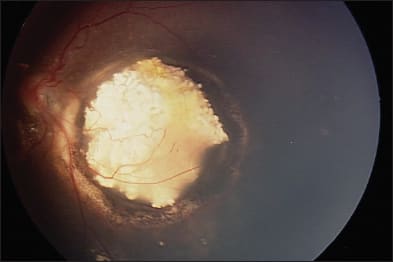

Figure 1. Left eye of a child with large macular retinoblastoma before treatment (top) and after intra-arterial melphalan and focal laser consolidation (bottom).